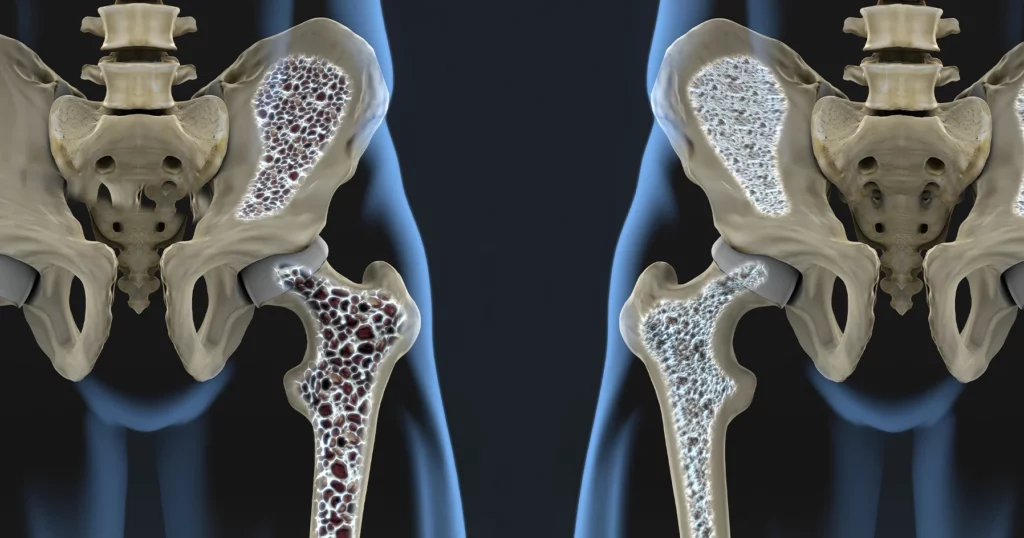

O echipă de cercetători din Germania anunță o descoperire revoluționară în tratamentul osteoporozei, o boală care afectează milioane de oameni la nivel global. Cercetările au identificat un receptor din organism, numit GPR133, care joacă un rol crucial în controlul rezistenței osoase. Activarea acestui receptor, în cadrul experimentelor pe animale, a dus la creșterea densității osoase și la refacerea țesutului afectat.

Cercetătorii de la Universität Leipzig au testat un nou compus, denumit AP503, care activează receptorul GPR133. Oasele sunt structuri dinamice, aflate într-un echilibru constant între celulele care construiesc os nou (osteoblaste) și cele care îl degradează (osteoclaste). Studiul a arătat că receptorul GPR133 influențează direct acest echilibru.

Când receptorul este activat, crește activitatea osteoblastelor și o reduce pe cea a osteoclastelor. „Dacă acest receptor este afectat, apar semne timpurii de pierdere a densității osoase, similare osteoporozei la oameni”, a explicat prof. dr. Ines Liebscher, coordonatoarea studiului. Stimularea receptorului cu AP503 a dus la o creștere semnificativă a rezistenței osoase, atât la animale sănătoase, cât și la cele cu probleme osoase.

Substanța AP503 a fost identificată cu ajutorul unor metode computerizate, permițând testarea rapidă a mii de molecule. Rolul acesteia este de a imita mecanismele naturale prin care organismul activează GPR133. Odată activat, receptorul transmite semnale care stimulează formarea de os nou, limitează degradarea osoasă și îmbunătățesc densitatea și rezistența țesutului.

Rezultatul este un os mai solid, mai puțin predispus la fracturi. În plus, echipa de cercetare a observat efecte pozitive și asupra masei musculare, aspect important pentru persoanele în vârstă. „Întărirea simultană a oaselor și a mușchilor arată potențialul uriaș al acestui receptor pentru aplicații medicale la persoanele în vârstă”, a menționat dr. Juliane Lehmann, autor principal al cercetării.